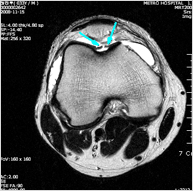

초기 손상은 단순 X-ray에서 발견되기 어려우며 MRI 로 진단할 수 있습니다. 하지만 MRI 도 정확한 병변의 크기나 손상된 연골과 주변의 싱싱한 연골과의 경계등 정확한 정보를 얻기에 부족한 부분이 있을 수 있습니다. 최종적인 상태 파악은 관절경으로 하게 되며 MRI 등으로 병변이 확인된 경우 수술 준비를 모두 갖추고 관절경을 하게 됩니다.

골수 자극법 - 천공술, 미세 골절술